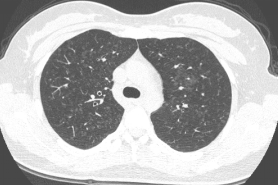

病例:女,59岁,鸽子肺,GGO+网格影+囊腔:

病例:男,62岁,未知抗原,GGO+实变影:

病例:男,65,饲鸟者肺,GGO+可能UIP型